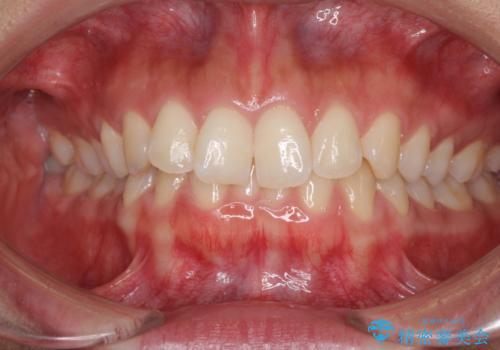

ワイヤーによる全体的ながたつきの矯正治療